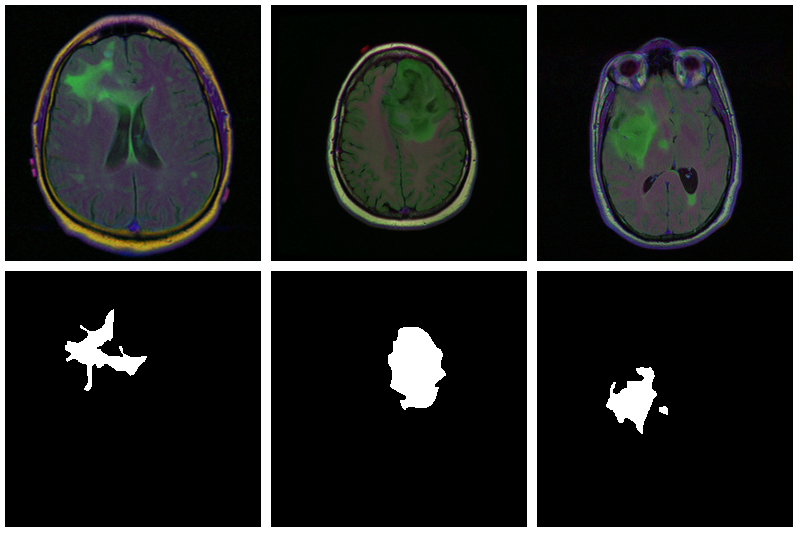

model$eval()Now, since we don’t have a separate test set, we already know the average out-of-sample metrics; but in the end, what we care about are the generated masks. Let’s view some, displaying ground truth and MRI scans for comparison.

par(mfcol = c(3, 8), mar = c(0, 1, 0, 1))

for (i in 1:8) {

img <- batch[[1]][i, .., drop = FALSE]

inferred_mask <- model(img$to(device = device))

true_mask <- batch[[2]][i, .., drop = FALSE]$to(device = device)

bce <- nnf_binary_cross_entropy(inferred_mask, true_mask)$to(device = "cpu") %>%

as.numeric()

dc <- calc_dice_loss(inferred_mask, true_mask)$to(device = "cpu") %>% as.numeric()

cat(sprintf("\nSample %d, bce: %3f, dice: %3f\n", i, bce, dc))

inferred_mask <- inferred_mask$to(device = "cpu") %>% as.array() %>% .[1, 1, , ]

inferred_mask <- ifelse(inferred_mask > 0.5, 1, 0)

img[1, 1, ,] %>% as.array() %>% as.raster() %>% plot()

true_mask$to(device = "cpu")[1, 1, ,] %>% as.array() %>% as.raster() %>% plot()

inferred_mask %>% as.raster() %>% plot()

}We also print the individual cross entropy and dice losses; relating those to the generated masks might yield useful information for model tuning.

Sample 1, bce: 0.088406, dice: 0.387786}

Sample 2, bce: 0.026839, dice: 0.205724

Sample 3, bce: 0.042575, dice: 0.187884

Sample 4, bce: 0.094989, dice: 0.273895

Sample 5, bce: 0.026839, dice: 0.205724

Sample 6, bce: 0.020917, dice: 0.139484

Sample 7, bce: 0.094989, dice: 0.273895

Sample 8, bce: 2.310956, dice: 0.999824

While far from perfect, most of these masks aren’t that bad – a nice result given the small dataset!